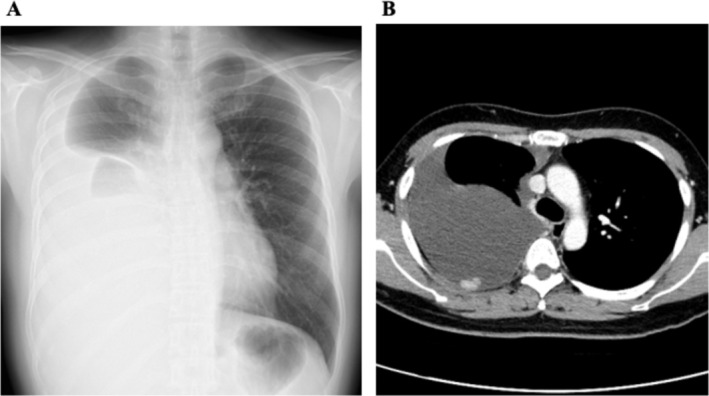

We report the case of a 41-year-old woman who developed an epithelioid-type pleural mesothelioma (PM) decades after treatment for childhood acute myeloid leukaemia (AML), who was treated with chemotherapy and total body irradiation (TBI). The diagnosis was confirmed by thoracoscopic pleural biopsy and immunohistochemical staining. Although PM is classically associated with asbestos exposure, the patient had no known history of exposure. This case report highlights the fact that PM can occur as a late-onset secondary malignancy following radiation therapy in childhood cancer survivors. Although radiation-induced PM has been reported primarily in survivors of Hodgkin lymphoma or breast cancer, incidences following treatment for leukaemia are exceptionally rare. This case report highlights the importance of considering prior therapeutic irradiation, including total-body irradiation, as a potential etiological factor for non-asbestos-related PM. It also emphasises the need for the long-term surveillance and monitoring of childhood cancer survivors, particularly those who have received radiation therapy.